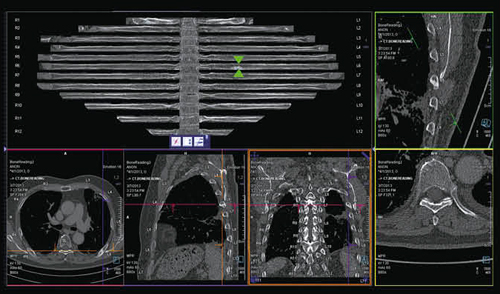

CT Bone Readingは,脊椎から肋骨の部分を展開した再構成画像を表示して骨転移の検索を容易にし,また,椎体および肋骨が自動でナンバリングされ,転移の位置,肋骨の位置などを簡単に把握できるようになっている。あらかじめ骨条件のthin sliceデータをsyngo.viaのサーバに送っておけば,スタディ名からCT Bone Readingの処理が自動で行われる(図6)。

図6 syngo CT Bone Reading(骨転移の検索)

脊椎,肋骨を一括表示し,自動ラベリング